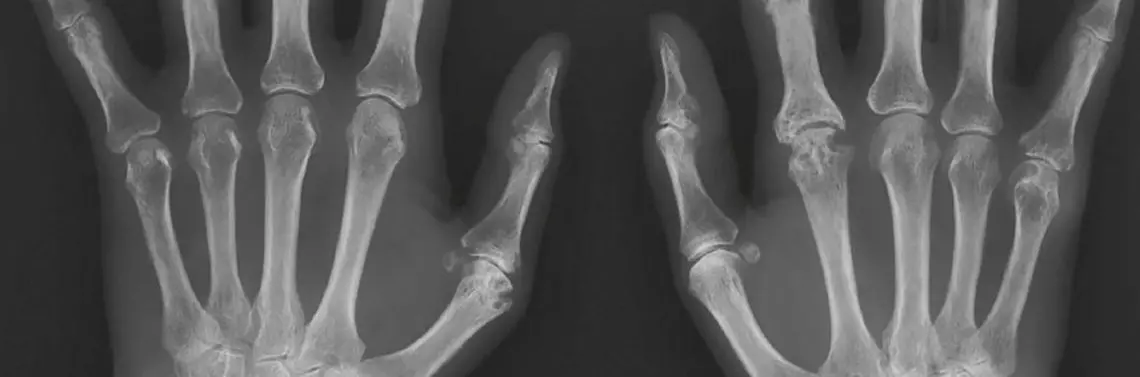

Niekiedy RTG pozwala odkryć również patologie tkanek miękkich w postaci złogów w rzucie przestrzeni podbarkowej – najczęściej są to złogi w kaletce podbarkowej lub w stożku rotatorów w przebiegu wapniejącego zapalenia ścięgien czy entezopatii. W przypadku stawu łokciowego wystarczają 2 projekcje – AP i boczna, ocenia się koncentryczne przyleganie nasad kostnych, szerokość szczeliny promieniowo-ramiennej (norma 2–3 mm), kąt fizjologicznej koślawości (norma ok. 15°) oraz kąt trzonowo-nasadowy (norma ok. 140°) szczególnie ważny u dzieci, gdzie widoczne jest tylko jądro kostnienia bloczka k. ramiennej i wobec zmian tego kąta wnioskuje się o złamaniu nadkłykciowym k. ramiennej. W przypadku nadgarstka stosuje się 2 podstawowe projekcje (AP i boczną) oraz kilka dodatkowych – skośne dla k. łódeczkowatej, w odwiedzeniu promieniowym i łokciowym oraz w pozycji zaciśniętej pięści (zdj. 4).